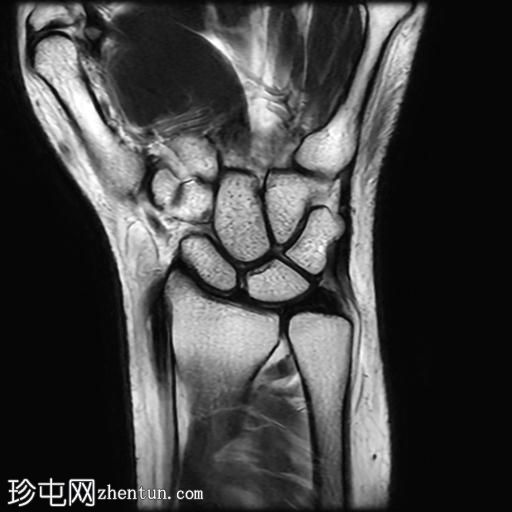

De Quervain腱鞘炎MRI

MRI显示腕部第一背侧肌腱(拇长展肌和拇短伸肌)增厚,并伴有异常增厚的实质内液体信号。腱鞘内液体增多。

尺侧腕伸肌腱可见异常线性实质内液体信号增多,与板状间质撕裂相关。

MRI表现和临床表现提示De Quervain腱鞘炎。